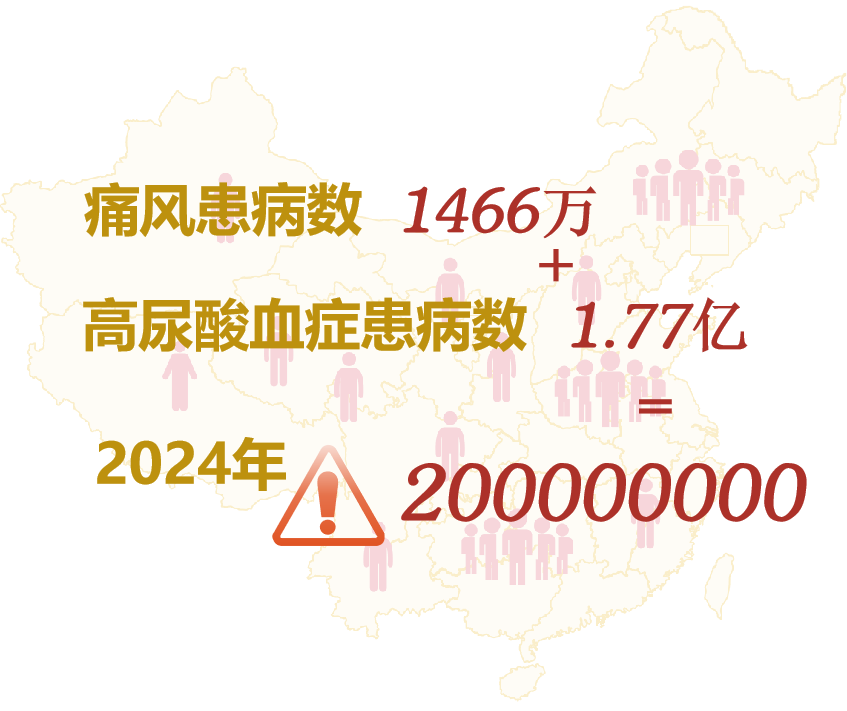

иҝ‘е№ҙжқҘ�пјҢ�пјҢ�пјҢжҲ‘еӣҪй«ҳе°ҝй…ёиЎҖз—Үе‘ҲжҳҫзқҖдёҠеҚҮе’Ңе№ҙиҪ»еҢ–и¶ӢеҠҝ�пјҢ�пјҢ�пјҢж•°жҚ®жҳҫзӨә�пјҢ�пјҢ�пјҢ2020е№ҙдёӯеӣҪй«ҳе°ҝй…ёиЎҖз—ҮжӮЈз—…дәәж•°зәҰдёә 1.77 дәҝ�пјҢ�пјҢ�пјҢз—ӣйЈҺжӮЈз—…дәәж•°зәҰдёә 1466 дёҮ�пјҢ�пјҢ�пјҢйў„и®ЎеҲ°2024е№ҙжҖ»дәәж•°е°ҶдёҖиҝһеўһж·»еҲ° 2 дәҝ[1]�гҖӮ�гҖӮгҖӮгҖӮ